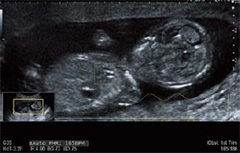

Otomatik FHR *

Fetal kalp hızı, B modu görüntüsündeki fetal kalp üzerindeki izlenen İlgi Alanı kullanılarak otomatik olarak hesaplanır. Bu özellik, geleneksel Doppler veya M modu yöntemlerine kıyasla daha güvenli veya daha nesnel ölçüm sunmaktadır. Bunun yanı sıra, bu fonksiyon transvajinal güç çevirici üzerinde kullanılabilir olduğundan, erken gebelikten itibaren değerlendirme yapılabilir.